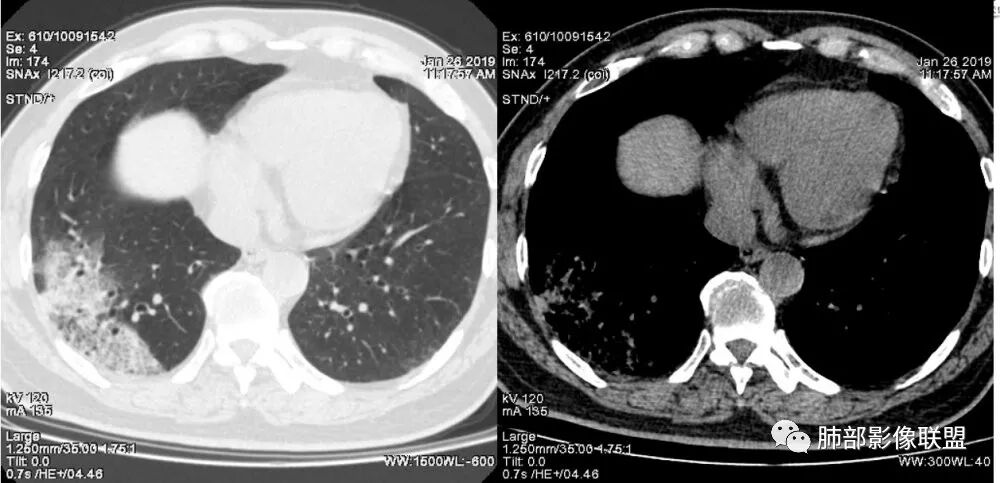

老年女性,右肺下叶沿胸膜下大片状高密度影,外周磨玻璃影,边界较清,内可见蜂窝征及支气管充气征,考虑肺炎型肺癌。

老年女性,咳嗽咳痰病史,右肺下叶大片磨玻璃实变影,胸膜下分布,支气管进入后扩张、僵直,磨玻璃影边界清楚,考虑粘液腺癌。鉴别肺炎。

中年女性,咳嗽咳痰。右肺下叶片状高密度影,部分实性密度,周围见边界清晰磨玻璃影,内见小空泡,实性区部分支气管堵塞,有重力效应,考虑肺炎型肺癌,建议查痰脱落细胞。

老年人,右肺下叶斑片状阴影,病灶有膨胀性,边缘可见磨玻璃影,其边界清晰,内见僵硬的支气管,部分支气管扩张,首先考虑占位性病变,粘液性腺癌可能。鉴别感染性病变,后者边缘多有收缩性改变或者平直,内部支气管走形自然。

右肺病灶,病灶较大,实性+周边ggo,边界清晰,胸膜下分布,长轴平行于胸膜,内部支气管充气征,因不发热,暂不考虑感染性病变,支持肺炎型肺癌。

我觉得纵膈窗可以更好观察,纵窗看支气管很紊乱的感觉,鉴别,肺炎的支气管充气征,支气管走形还是很自然的

1.本例病灶较大片混杂密度影,胸膜下分布为主(未沿着支气管分布),该分布特点可见于大叶性肺炎、干酪性肺炎、淋巴瘤及粘液腺癌等。可惜未提供增强扫描图像。

2.病灶示中央实变区,周围GGO,可见明显小叶间隔增厚,GGO边界清楚,应当考虑到恶性病变的可能性。肺炎因炎性水肿及渗出,影像上边界常模糊不清,注意早期粘液腺癌可出现似清非清的边界。粘液腺癌因粘液成份较多,密度一般偏低,纵隔窗病灶常会消隐或范围会明显缩小,这不同于炎性实变。

3.病灶内支气管走形略显僵直,侧支少(粘液阻塞),也符合肺腺癌的枯树枝征。而大叶性肺炎的支气管是管壁光整、通畅、自然,结核的支气管常常壁增厚,甚至狭窄后扩张;

4.患者临床症状不重,临床炎性指标不高,结合肺内影像,应警惕肺炎型肺癌。